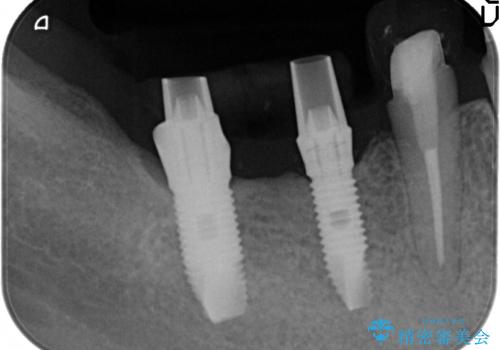

残すことのできる歯できない歯を選別し、欠損部にはインプラントによる咬合機能の回復、保存できる歯には歯周病治療・根管治療を行う治療計画としました。